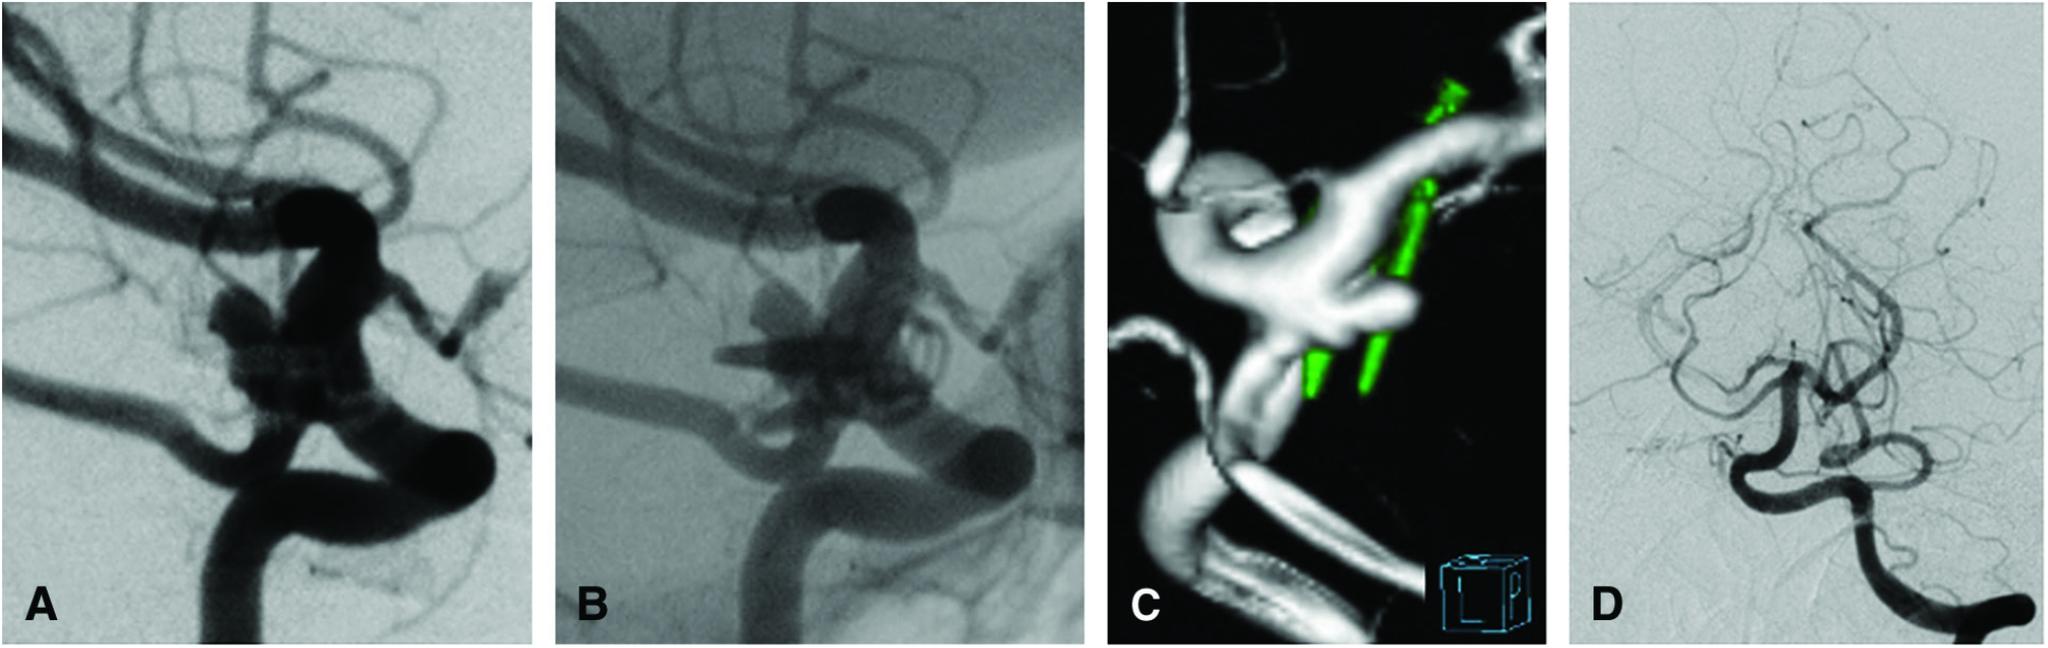

We report a case in which coil embolization using crossing Y-configuration stenting was effective for an internal carotid-posterior communicating artery (IC-PC) aneurysm with repeated recurrence after clipping.

The patient was a 57-year-old woman. Nine months after undergoing clipping for a ruptured right IC-PC aneurysm at 55 years of age, she developed a second subarachnoid hemorrhage (SAH) due to recurrence of the aneurysm and underwent clipping at the same site. A third SAH due to rupture of the left IC-PC aneurysm developed 1.5 years after the second clipping. Simultaneously, recurrence of a right IC-PC aneurysm was noted and she was referred to our department. The recurrent right IC-PC aneurysm was considered to have originated from the distal to the initial neck. It was 7 mm in size and had an irregularly shaped wide neck. As it was assumed that there would be marked adhesion due to repeated surgery, we decided to treat the aneurysm by coil embolization instead of direct surgery. Although the aneurysm neck partially involved the posterior communicating artery (Pcom), tight packing with a minimal residual neck was required. Therefore, crossing Y-configuration stenting was deployed on the internal carotid artery and Pcom using two Neuroform Atlas stents, and coil embolization was performed by the jail technique. The recurrent aneurysm was obliterated. There were no deficits or thrombotic complications after surgery. On DSA follow-up, no compaction or recurrence was observed, and the Pcom was well visualized one year later.

患者为一名57岁女性。55岁时因右侧IC-PC动脉瘤破裂行夹闭术,9个月后因动脉瘤复发出现第二次蛛网膜下腔出血(SAH),并在同一部位再次行夹闭术。第二次夹闭术后1.5年,因左侧IC-PC动脉瘤破裂出现第三次SAH。同时,发现右侧IC-PC动脉瘤复发,遂转诊至我科。复发性右侧IC-PC动脉瘤被认为起源于初始瘤颈的远端。其大小为7mm,瘤颈宽且形状不规则。由于考虑到反复手术会导致明显粘连,我们决定采用弹簧圈栓塞而非直接手术治疗该动脉瘤。尽管动脉瘤颈部分累及后交通动脉(Pcom),但仍需要紧密填塞以使残留瘤颈最小化。因此,使用两枚Neuroform Atlas支架在颈内动脉和Pcom上部署交叉Y形支架,并采用“jail技术”进行弹簧圈栓塞。复发性动脉瘤被完全闭塞。术后无神经功能缺损或血栓形成并发症。DSA随访显示,术后一年未见弹簧圈压缩或复发,Pcom显影良好。